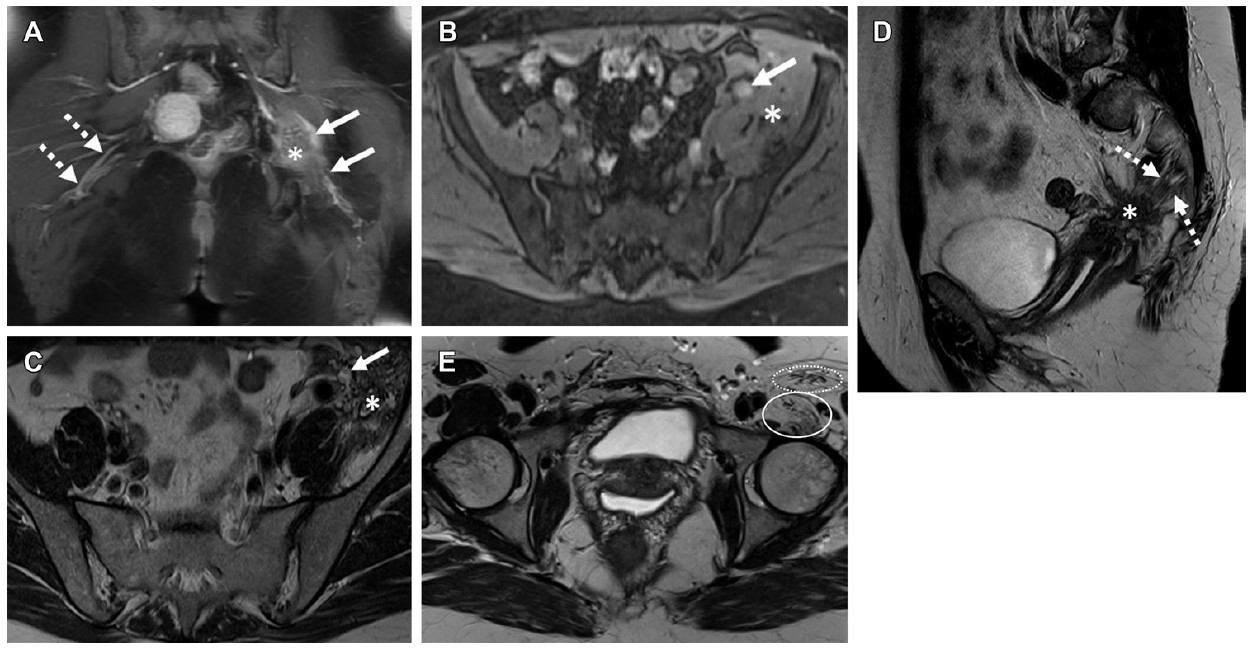

The ScanTrainer endometriosis module takes the user through ultrasound evaluation of the pelvis, and it includes clinical cases that help users identify disease in the bladder, bowel, and ovaries.